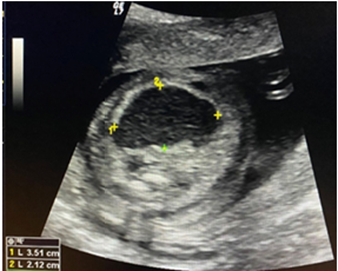

Acudió a la Unidad de Perinatología, realizándose ecografía morfológica del segundo trimestre. Se evidenció en abdomen fetal, por debajo del estómago y adyacente a la vejiga, una imagen hipoecoica de bordes irregulares, que midió 14 x 13 mm, doppler negativo. Se corroboró inserción de cordón umbilical adecuada en abdomen fetal e integridad de la pared del mismo. No se evidenciaron otros hallazgos asociados. Se planteó probable patología gastrointestinal tipo quiste de duplicación intestinal (Figura 1-2).

Figura 1 Ecografía morfológica a las 18 semanas, se observa imagen hipoecoica, irregular que mide 14 x 13 mm (T), vejiga (V).